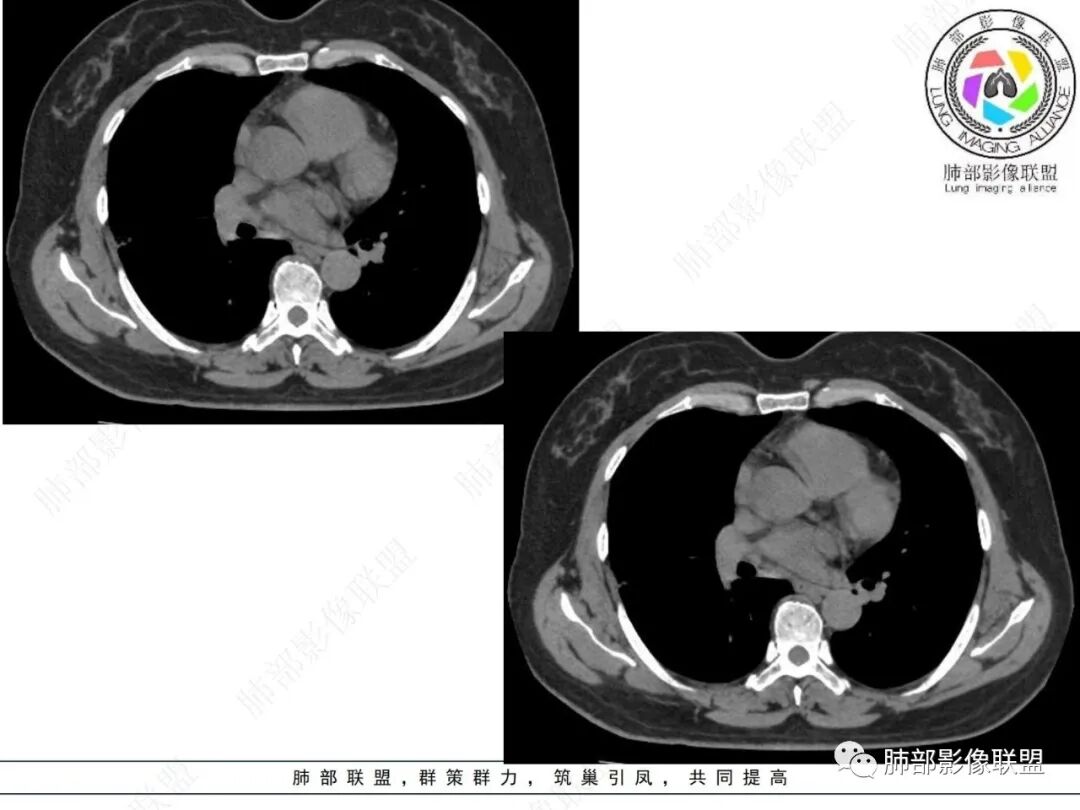

实性部分较密实,不规则,隐约见棘突或刺状突起,未见钙化、空洞或液化区,实性边缘可见斑状略低密度间隙(借用王兆宇老师课件,称其呈“松软”的形态)。动脉期实性部分较明显不均匀强化,如果有完整增强图,还可以观察内部血管情况。

纵隔窗相对肺窗病灶相对小,仅部分实性影呈现。病灶张力不高,相邻胸膜增厚(糊墙),未见明显胸膜牵拉凹陷。

病灶磨玻璃部分边界较清楚,有重力分布趋势,可能会想到黏液腺癌,或者分泌粘液的腺癌的可能性。不支持地方也有,如实性部分密度偏高,病灶强化程度偏高等。

其他需要鉴别的原有病灶伴出血,炎性病灶等等,感染性病变需要排除的尚有隐球菌,临床表现逍遥,病灶未出胸膜下,周围磨玻璃等等……

经验性抗炎治疗,病灶活检是较好的鉴别方式。单就影像而言,复查病灶进行性进展,沿支气管出现播散灶也是粘液腺癌诊断的有力证据。